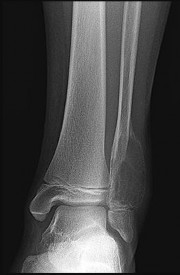

Figures 9a through 9d are the anteroposterior and lateral radiographs, CT scan, and technetium bone scan of a 12-year-old boy who has experienced 7 months of pain in his lower leg. The pain limits his ability to participate in sports and he is having difficulty sleeping. He is afebrile, and laboratory study findings including an erythrocyte sedimentation rate, C-reactive protein, and complete blood count are within normal limits.

The images and clinical history support a diagnosis of osteoid osteoma, which most commonly occurs in adolescence. Although these lesions can be seen in any bone, they are usually located in the femur and tibia. The significant inflammatory response to this tumor is secondary to high levels of prostaglandin production. Characteristic night pain is relieved with nonsteroidal anti-inflammatory drugs (NSAIDs) or by aspirin.

Radiographic images show thickened bone and a small central nidus. Thin-cut CT scan is the imaging of choice to visualize the nidus. A bone scan is associated with uptake but is not specific. Treatment options include expectant management with NSAIDs and observation under the premise that these lesions eventually burn out. Contemporary treatment involves RFA. Historically, these lesions were treated with en bloc resection; however, this technique has largely fallen out of favor because of the high efficacy and comparative low morbidity associated with RFA.

When an osteoid osteoma occurs in the spine, it is located in the posterior elements, and paraspinal pain and scoliosis often are present.